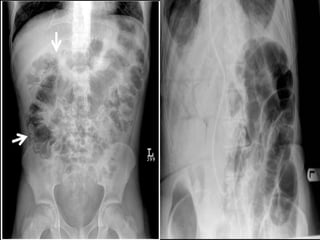

ABDOMINAL PLAIN

RADIOGRAPH

 Gas filled, dilated small bowel loops with air fluid

levels.

 Thumb printing sign (thickening of bowel wall +

valvulae (edema)

 Pneumatosis intestinalis.

 Mesenteric + portal vein gas